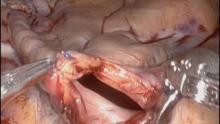

Upon establishment of peripheral CPB and placement of an aortic root vent and right superior pulmonary vein left ventricular vent, transthoracic aortic cross-clamping was performed. An aortotomy then facilitated direct coronary ostial cardioplegia delivery to establish myocardial arrest. Under full robotic assistance, the left atriotomy was performed and the PFO was closed primarily. A complete biatrial Cox maze with cryoablation was performed, followed by left atrial appendage obliteration using established biatrial lesions (3). Mitral valve repair involved triangular resection of P2 supported by a 38mm posterior annuloplasty band.

Finally, excellent exposure of the aortic valve leaflets facilitated resection, circumferential 2-0 braided annular suture placement, and implantation of a 25mm bioprosthesis, followed by aortotomy closure with 4-0 running monofilament suture in two layers to complete the RAVR.